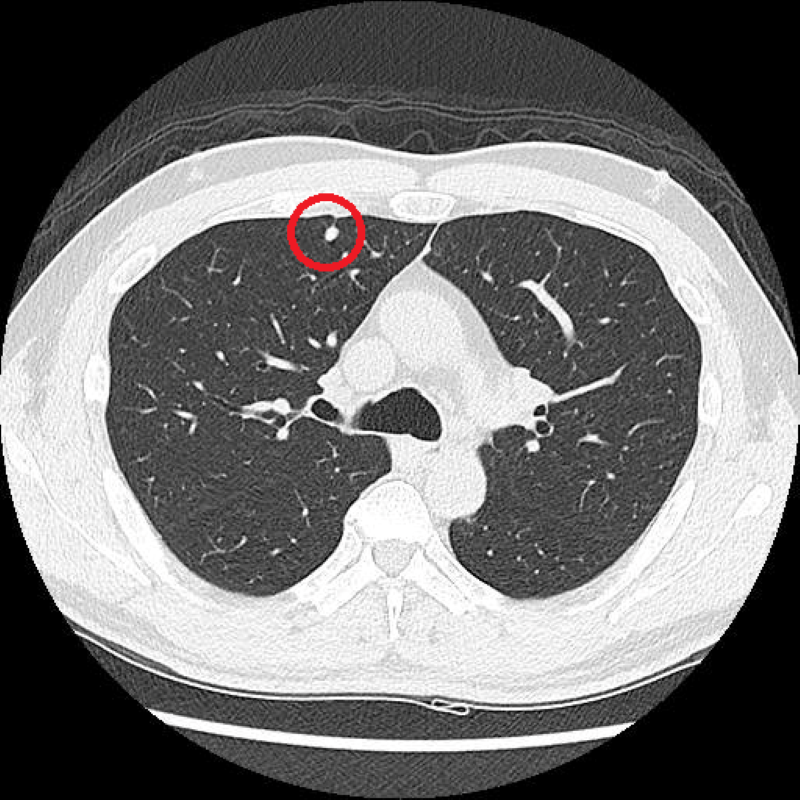

低劑量電腦斷層(LDCT)在肺癌的篩檢日漸普及,但篩檢出微小結節後是否需要切除,也成為許多人的疑問。對此,台北慈濟醫院胸腔外科陳東仁醫師指出,肺結節不等於肺癌,更不代表一定要立刻開刀,臨床上會依照病灶大小、型態、位置及變化綜合判斷。加上肺癌治療已朝向精準醫學發展,對於部分位置或大小難以掌握的肺部病灶,可以透過術前電腦斷層染色定位或螢光定位,盡量縮小切除範圍,保留更多正常肺葉與肺功能。以61歲黃先生為例,戒菸一段時間的他主動接受LDCT篩檢後,發現右上肺有一顆約0.5公分的肺部結節,考量影像沒有高度惡性特徵,陳醫師安排他持續追蹤觀察,若有變大趨勢再進一步討論醫療方針。

陳東仁醫師說明,針對篩檢出的微小結節,醫師無法單從影像直接判定良性或惡性。「根據國際指引,實質性的結節必須超過0.8公分或持續增大才會建議處理,但民眾若能定期追蹤,一旦出現變化,便能及早治療,而若能在早期就確診並接受適當治療,患者的五年存活率可高達九成。」陳醫師進一步說明,即便是真正需要處理的病灶,醫師也會依照大小、位置及臨床評估決定治療方式,若是早期腫瘤、體積小或位置較深,手術中有時不易用肉眼或觸感精準找到病灶,因此現在可在手術前先進行電腦斷層導引染色定位或螢光定位,協助術中快速辨識腫瘤位置,再用微創的方式進行手術。不僅提升切除精準度,也能避免切除過大的肺部範圍,盡量保留更多正常肺葉,減少不必要的正常組織切除。